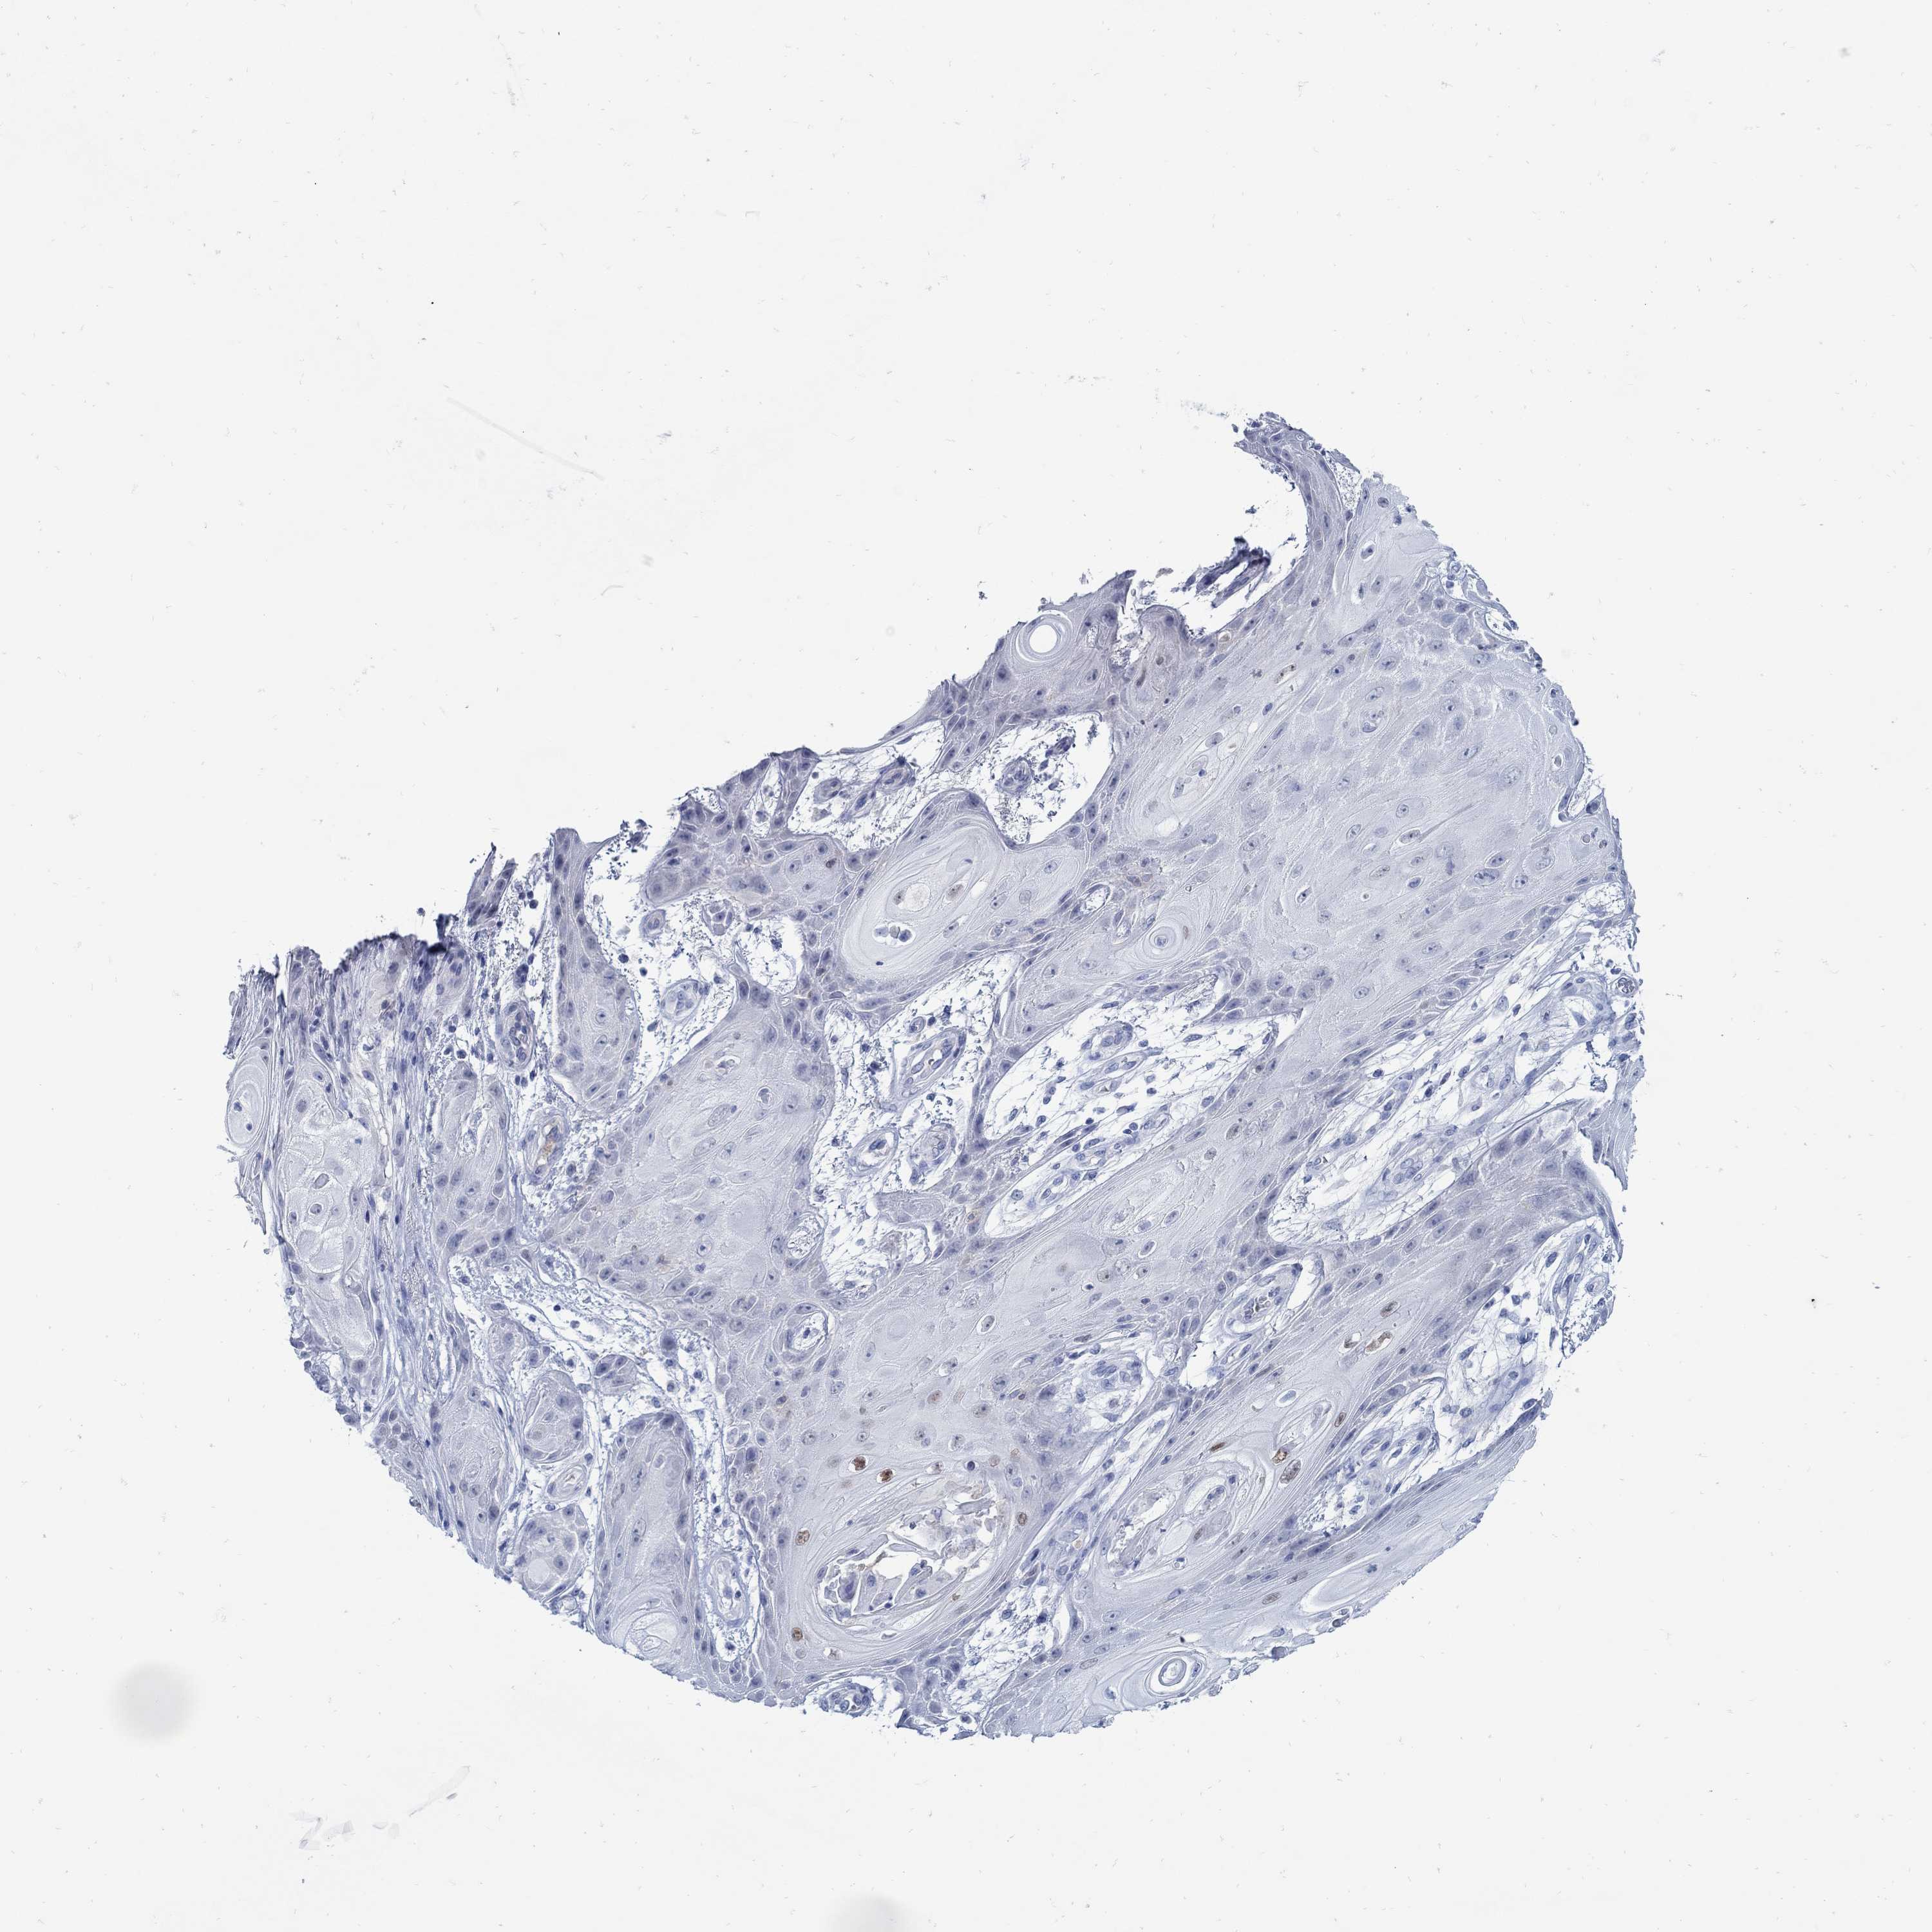

CANCER SKIN CANCER Show tissue menu

Basal cell and squamous cell cancer

SKIN CANCER - Protein expressioni

A mouse-over function shows sample information and annotation data. Click on an image to view it in a full screen mode. Samples can be filtered based on level of antibody staining by selecting one or several of the following categories: high, medium, low and not detected. The assay and annotation is described here.

Each image is clickable and will lead to virtual microscopy that enables deeper exploration of all samples and also displays staining intensity scores, fraction scores and subcellular localization as well as patient and tissue information for each sample.

Antibody CAB016239

Staining

High

Medium

Low

Not detected

Intensity

Strong

Moderate

Weak

Negative

Quantity

>75%

75%-25%

<25%

None

Location

Nuclear

Cytoplasmic/membranous

Cytoplasmic/membranous,nuclear

Basal cell carcinoma

Squamous cell carcinoma, NOS